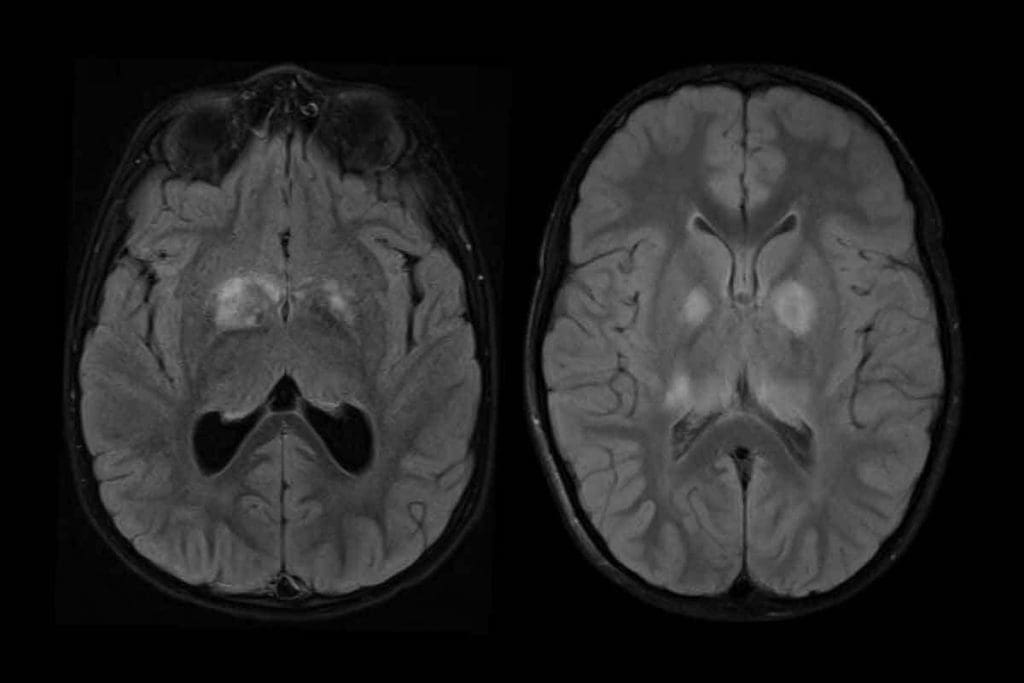

Ring Enhancement vs. Homogeneous Enhancement

CT scans can show different enhancement patterns in masses. These patterns help us figure out what the mass might be. Ring enhancement and homogeneous enhancement are two common types.

- Ring enhancement shows a ring of enhancement around a central area. This is often seen in high-grade tumors, abscesses, or metastases.

- Homogeneous enhancement means the whole mass enhances evenly. This is more typical of certain tumors, like meningiomas or some primary brain tumors.

Knowing these patterns helps us narrow down what the mass could be. It guides our next steps in managing the patient.

Differential Diagnosis Based on Enhancement

The enhancement pattern on a CT scan is key to making a diagnosis. We look at the enhancement pattern, the mass’s location, size, and how it affects the brain. This helps us make a more accurate diagnosis.

A ring-enhancing lesion might suggest a brain abscess or a high-grade glioma. A homogeneously enhanced mass could be a meningioma or a metastatic tumor. The clinical context and other imaging findings also help refine the diagnosis.

Metastatic Disease Presentation

Brain metastases are common, mainly in cancer patients. On CT scans, they look like multiple, well-defined lesions at the gray-white junction. They often show ring enhancement after contrast, but this can vary.

Non-Neoplastic Masses (Abscesses, Granulomas)

Non-neoplastic masses, like abscesses and granulomas, can look like tumors on CT scans. Abscesses are ring-enhancing with a hypodense center. Granulomas, linked to conditions like tuberculosis or sarcoidosis, can be solid or ring-enhancing.